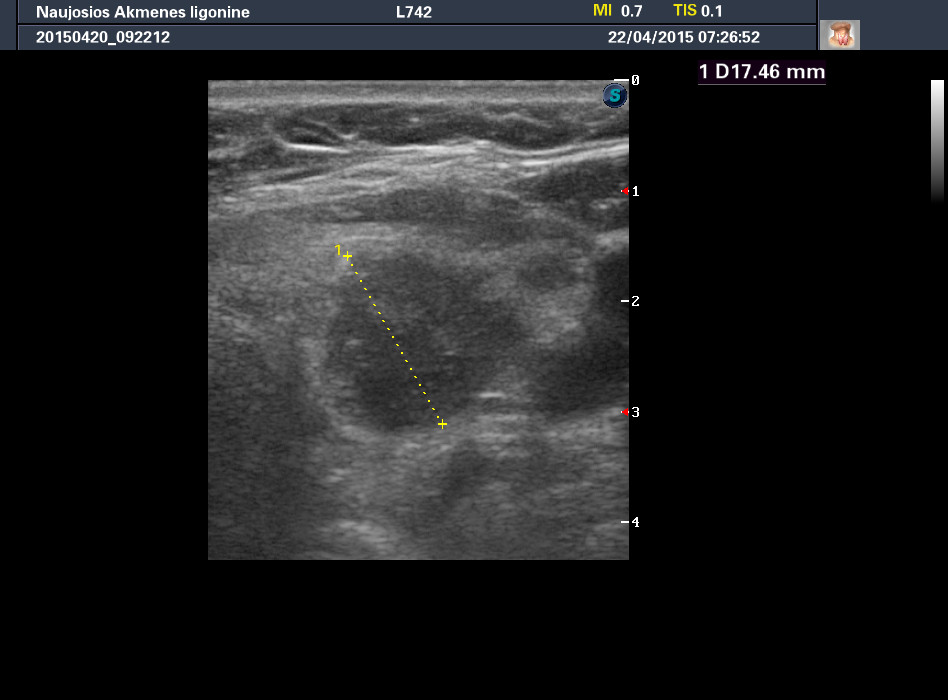

Случай 1

Женщина 67 лет, жалоб нет. Рост узла за год +3 мм. Регионарные ЛУ не увеличены.

apr222015072652_0.jpg

Цитология 1 случая - злокачественных клеток не обнаружено.

Обычно фолликулярный эпителий, кровь, коллоид.

Но в данном конкретном случае ответ был именно таким - "злокачественных клеток не обнаружено".